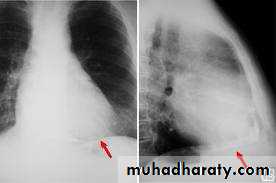

CXR – ECHO

CXR: Useful if there is effusionECHO :can detect even small amount

CXR : 250 ml positive

Ecg + CXR + ECHO

-CXR-Increase cardiac sillhoutte

Flask shaped enlargement

CXR- small heart -Calcification